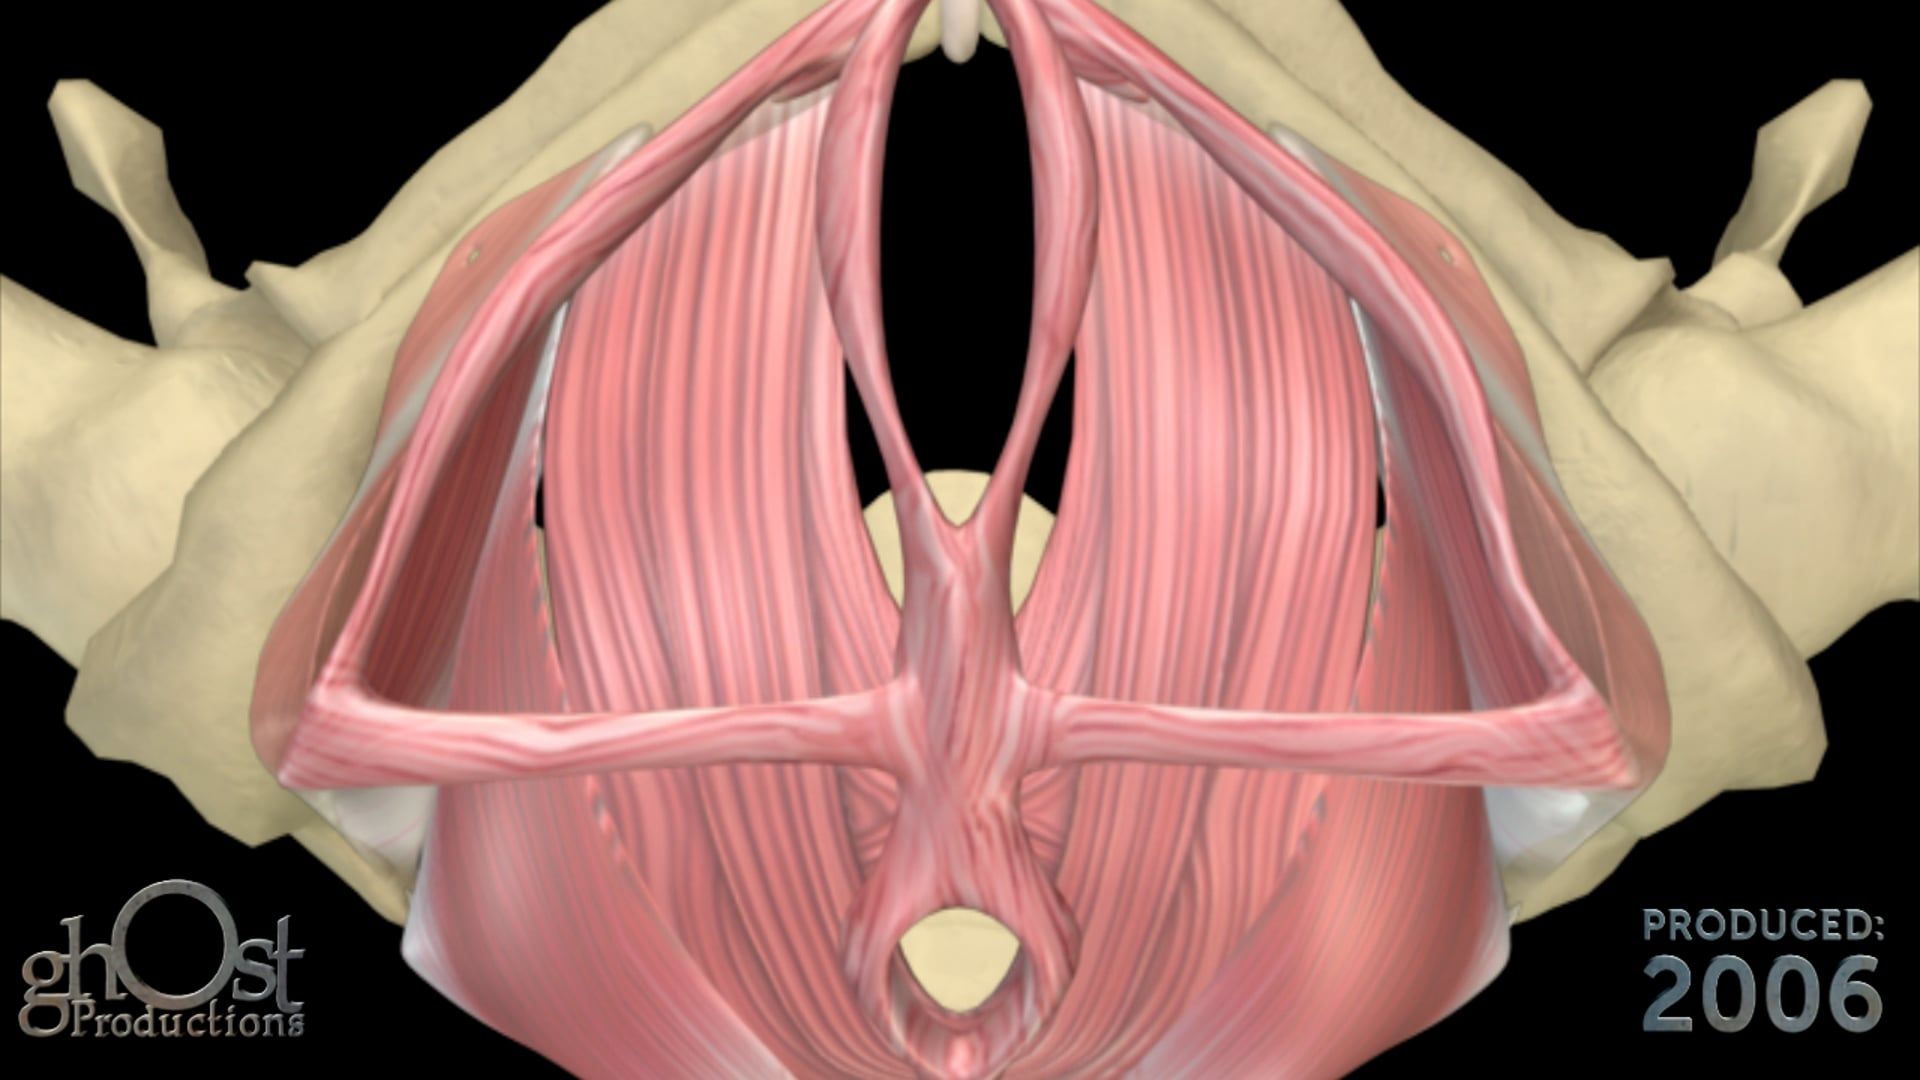

Looking for a reliable and effective bladder anchored urinary catheter with retractable tines? Look no further than the AMS Continuum, brought to life in stunning detail in this animation from Ghost Productions. Our team worked closely with American Medical Systems to create a visual representation of this innovative medical device, highlighting its unique features and benefits. Whether you're a healthcare provider looking for the latest in urinary catheter technology or a patient seeking a more comfortable and secure solution, the AMS Continuum is a game-changer. Watch our animation today to learn more!